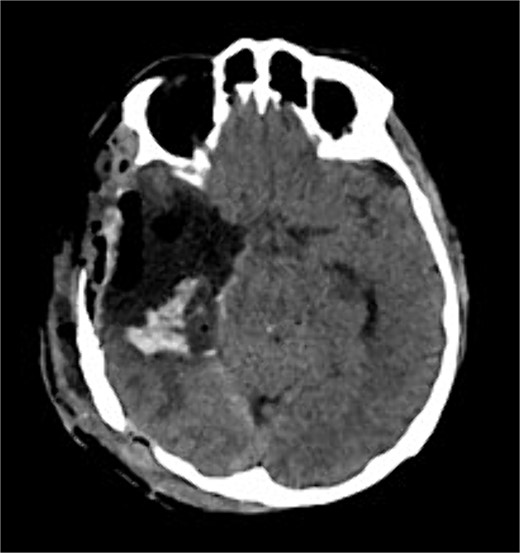

The patient underwent a right temporo-parietal craniotomy for lesion resection (Fig. 3), followed by radiotherapy and temozolomide, and was transferred to the neuro intensive care unit for close monitoring. Postoperatively, the patient remained conscious, alert, and oriented, with stable vital signs, but exhibited left facial paresis, diminished vision in the right eye, and left-sided weakness. Pathological assessment confirmed a high-grade glioma, consistent with a World Health Organization grade IV tumor (Fig. 4). It revealed an infiltrative, hypercellular astrocytoma characterized by hyperchromatic, elongated nuclei with irregular contours. A significant number of mitotic figures were observed. The histopathological assessment also demonstrated geographic and pseudopalisading necrosis, accompanied by microvascular proliferation, which are hallmark features of high-grade gliomas.

Postoperative axial CT shows postoperative changes with maximum safe resection of the lesion. CT = computed tomography.